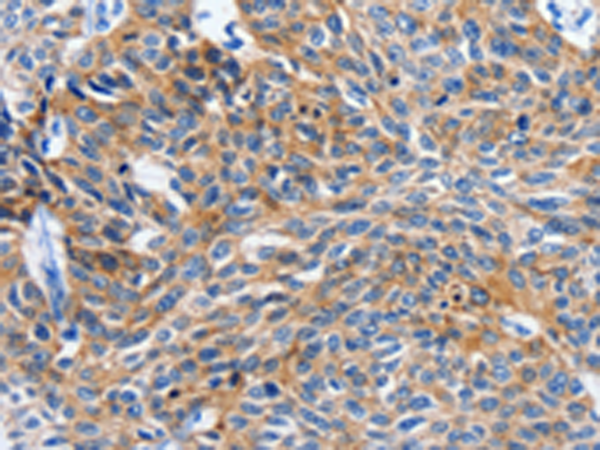

分类: 科研抗体货号: P04117别名: MMP25; MMP-24; MT5MMP; MTMMP5; MT-MMP5; MT5-MMP; MT-MMP 5应用: IHC反应种属: Human, Mouse, Rat